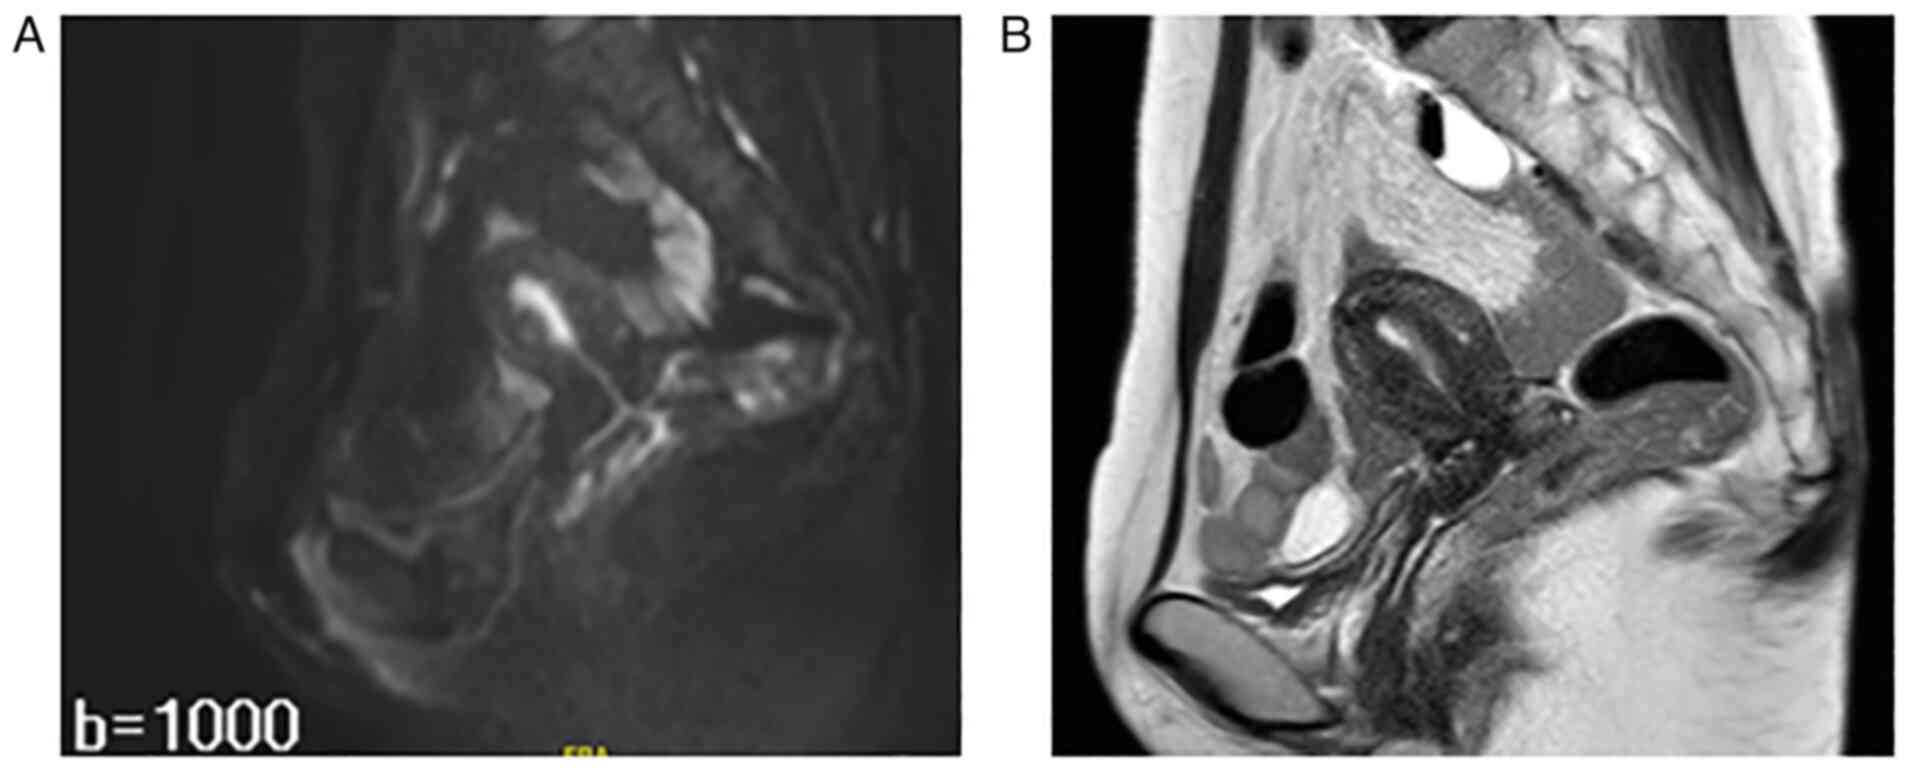

The association between endometrial cancer and the BRCA1 and BRCA2 genes is not fully understood, and the risk elevation of endometrial cancer in patients with hereditary breast and ovarian cancer (HBOC) is not understood. The present report examines a rare case of HBOC syndrome and an uncharacterized variant of the BRCA1 gene in a patient diagnosed with endometrial cancer. A 46‑year‑old woman, gravida 1 para 1, was referred to Wakayama Medical University Hospital (Wakayama, Japan) because positron emission tomography/computed tomography (PET/CT) showed a high FDG uptake in the corpus uteri and the left ovary. PET/CT was performed just after mastectomy for left‑sided breast cancer (triple negative). The patient had previously undergone partial mastectomy for right‑sided breast cancer (triple negative) and was treated with radiation therapy to the right residual breast when she was 39 years old. Laparoscopic hysterectomy and bilateral adnexectomy were performed, and the histological diagnosis was endometrioid carcinoma, grade 1. Her germline BRCA status was tested by blood examination and the result was ‘NM_007294.4(BRCA1):c.49G>C (p.Ala17Pro)’. The variant was evaluated as ‘likely pathogenic’. The patient was diagnosed with HBOC syndrome and endometrial cancer, pT1ANxM0. The patient had no recurrence of breast or endometrial cancer 16 months after gynecologic surgery.